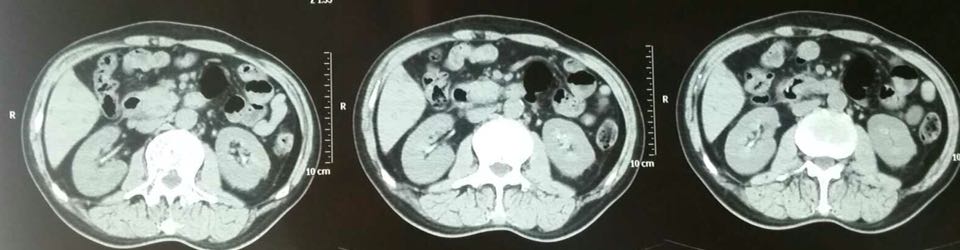

男,50岁,主因发现皮肤黄染两月入院,片子看下面,各位考虑什么?

胆管癌